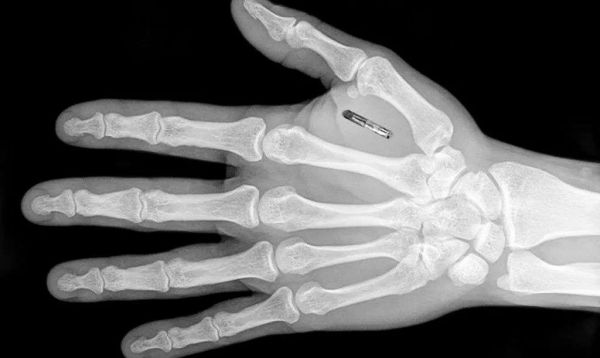

植入体内的微芯片,也已踏上商业化进程、并启动有限范围的试验。

BioHax公司创始人曾在2018年公开宣称:仅在瑞典,即有约4000人已植入微芯片,国外也有同等量级的试用者。通过读取芯片,可以准确识别、验证或追踪个体。目前,这一技术已经或即将投入实践的应用场景包括:乘客登车时,读取芯片来验证身份;公司出于安全防护的内部识别和验证;超市识别顾客等。

图片来源:BioHax

微芯片带来和起搏器相似的隐私难题是:有关这些芯片上的信息,即使植入时的目的相当明确,后续出现类似公共利益的考量时,这些信息依然可能为个体带来意想不到的麻烦。再进一步说,在物联网设备随处可见的当下,这些信息有没有可能匹配、融合,微芯片有没有可能和其它设备组网、联动,都不再是“科幻”式的追问,而是如果想做、技术即可实现的选项。